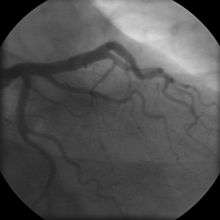

Coronary angiogram of a man

For symptomatic patients, stress echocardiography can be used to make a diagnosis for obstructive coronary artery disease.[50] The use of echocardiography, stress cardiac imaging, and/or advanced non-invasive imaging is not recommended on individuals who are exhibiting no symptoms and are otherwise at low risk for developing coronary disease.[50][51]

The diagnosis of "Cardiac Syndrome X" - the rare coronary artery disease that is more common in women, as mentioned, an "exclusion" diagnosis. Therefore, usually the same tests are used as in any patient with the suspicion of coronary artery disease:

The diagnosis of coronary disease underlying particular symptoms depends largely on the nature of the symptoms. The first investigation is an electrocardiogram (ECG/EKG), both for "stable" angina and acute coronary syndrome. An X-ray of the chest and blood tests may be performed.

In "stable" angina, chest pain with typical features occurring at predictable levels of exertion, various forms of cardiac stress tests may be used to induce both symptoms and detect changes by way of electrocardiography (using an ECG), echocardiography (using ultrasound of the heart) or scintigraphy (using uptake of radionuclide by the heart muscle). If part of the heart seems to receive an insufficient blood supply, coronary angiography may be used to identify stenosis of the coronary arteries and suitability for angioplasty or bypass surgery.